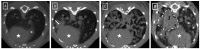

In this study, we present a time-efficient protocol for thoracic volume calculation as a proxy for total lung volume. We hypothesize that lung volume can be calculated indirectly from this thoracic volume. We compared the measured thoracic volume with manually segmented and automatically thresholded lung volumes, with manual segmentation as the gold standard. A linear regression formula was obtained and used for calculating the theoretical lung volume. This volume was compared with the gold standard volumes. In healthy animals, thoracic volume was 887.45 mm3, manually delineated lung volume 554.33 mm3 and thresholded aerated lung volume 495.38 mm3 on average. Theoretical lung volume was 554.30 mm3. Finally, the protocol was applied to three animal models of lung pathology (lung metastasis and transgenic primary lung tumor and fungal infection). In confirmed pathologic animals, thoracic volumes were: 893.20 mm3, 860.12 and 1027.28 mm3. Manually delineated volumes were 640.58, 503.91 and 882.42 mm3, respectively. Thresholded lung volumes were 315.92 mm3, 408.72 and 236 mm3, respectively. Theoretical lung volume resulted in 635.28, 524.30 and 863.10.42 mm3. No significant differences were observed between volumes. This confirmed the potential use of this protocol for lung volume calculation in pathologic models.